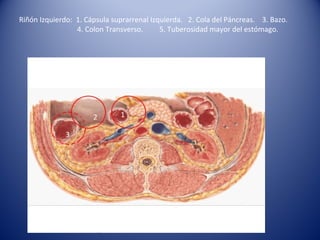

Riñón Izquierdo: 1. Cápsula suprarrenal Izquierda. 2. Cola del Páncreas. 3. Bazo.

4. Colon Transverso. 5. Tuberosidad mayor del estómago.